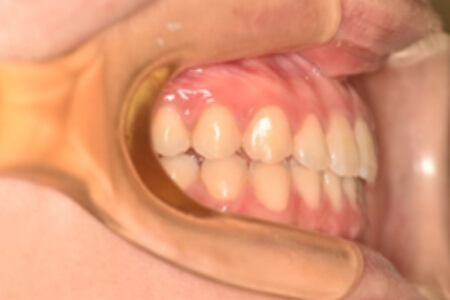

動的治療終了時

治療内容の詳細 初診時21歳の女性で、上顎前歯部の隙間(正中離開)を主訴として来院されました。

検査の結果、上下顎前歯部に空隙を伴うアングルⅠ級不正咬合と診断しました。

治療としては、非抜歯の上、マウスピース矯正装置(インビザライン)で配列を行いました。

治療期間は、1年9か月でした。